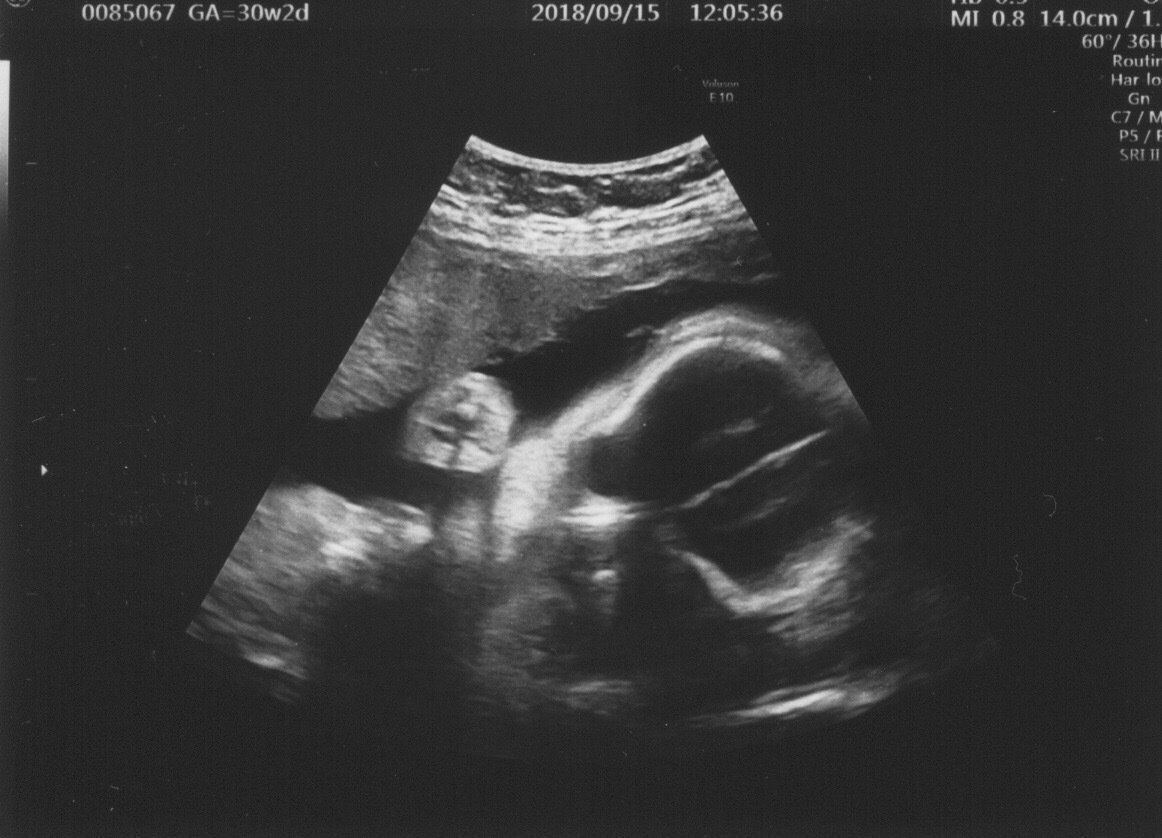

妊娠30週目 逆子になっていた息子

妊娠後期になると胎動も激しくなり、おなかを蹴られては「今日も元気だな」と安心して過ごしていました。しかし、あるときから、胎動のたびにものすごくトイレに行きたくなるように。不思議に思っていたら、健診で逆子になっていることが発覚!

ちょうど足が膀胱のあたりにあったので、トイレに行きたくなったようです。

「いまの段階なら、勝手に(逆子から)戻るから大丈夫」という先生の言葉通り、次の健診のときには元に戻っていて一安心しました。